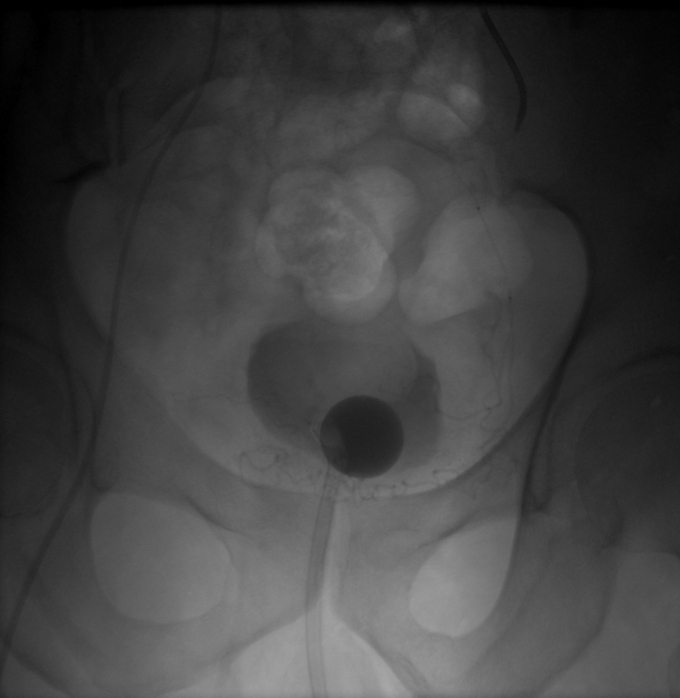

أدخل فريق وحدة الأشعة التداخلية بمستشفى النور التخصصي بمكة المكرمة بالتعاون مع قسم جراحة المسالك البولية خدمة جديدة وهي علاج تضخم البروستات الحميد المؤدي إلى احتباس البول عن طريق الأشعة التداخلية.

وأكدت صحة مكة المكرمة أنه تم تقديم هذه الخدمة لمريض سبعيني يعاني من احتباس البول المزمن بسبب تضخم البروستات الحميد وعدم الاستجابة للأدوية والاعتماد الكلي على قسطرة البول.

ونظراً لحالة المريض الصحية والتي تجعل من الجراحة التقليدية إجراء عالي الخطورة فقد تم تحويل المريض لأطباء وحدة الأشعة التداخلية والذين عاينوا المريض وراجعوا الفحوصات لعمل الأشعة اللازمة ومن ثم إجراء العملية التداخلية باستخدام التخدير الموضعي فقط.

وأضافت صحة مكة أنه عند متابعة المريض على مدار الأشهر التالية فقد تحسن فيها احتباس البول بشكل كبير وتمت إزالة قسطرة البول بشكل نهائي.

تجدر الإشارة إلى أن هذا الإجراء الطبي يعتبر أحد الإجراءات الطبية الحديثة والمثبتة علمياً بمنفعتها لمثل هؤلاء المرضى.